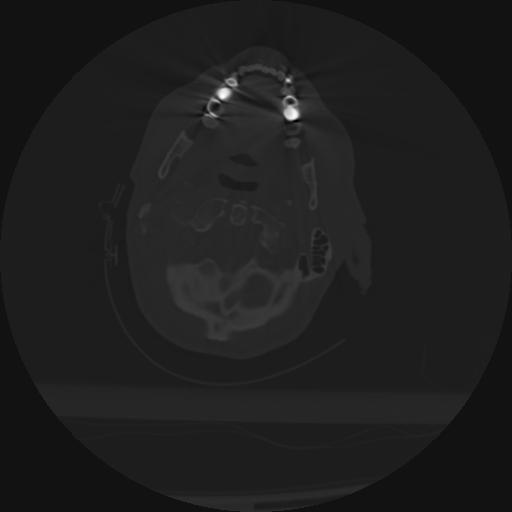

22 ANGIO,CE,Vol,0.5,ANGIO,,